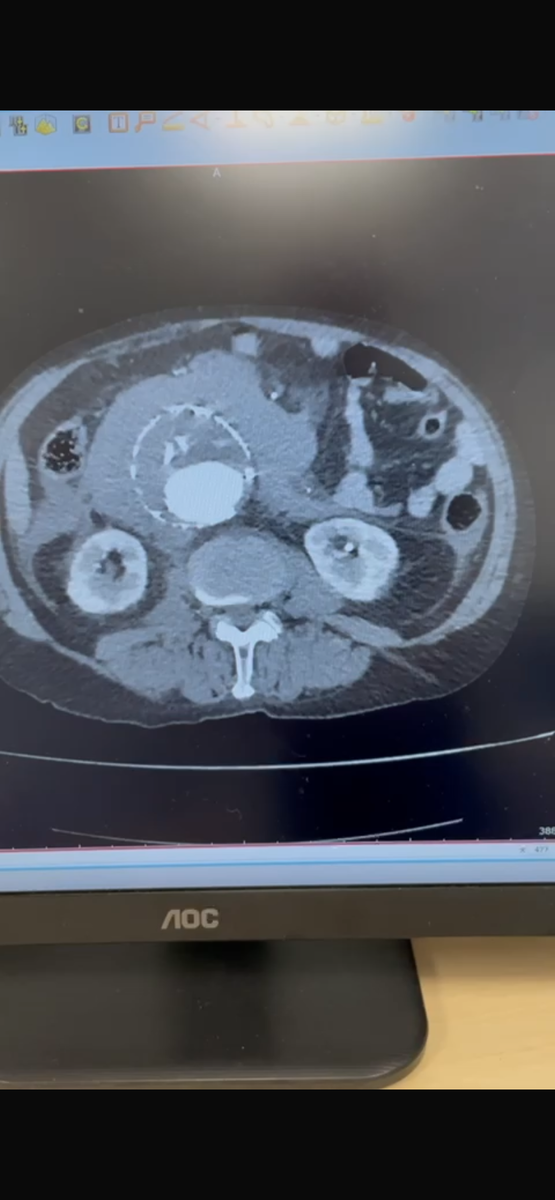

Что делать, если у вас обнаружили аневризму брюшного отдела аорты?

Аневризма представляет собой расширение стенки аорты, которое может привести к ее разрыву и, как следствие, к жизни угрожающим состояниям. Очень часто это случайная находка.

• В-третьих, важно проходить регулярные медицинские обследования. Врач может назначить МСКТ для контроля за изменениями в размере аневризмы и для оценки состояния кровеносных сосудов.